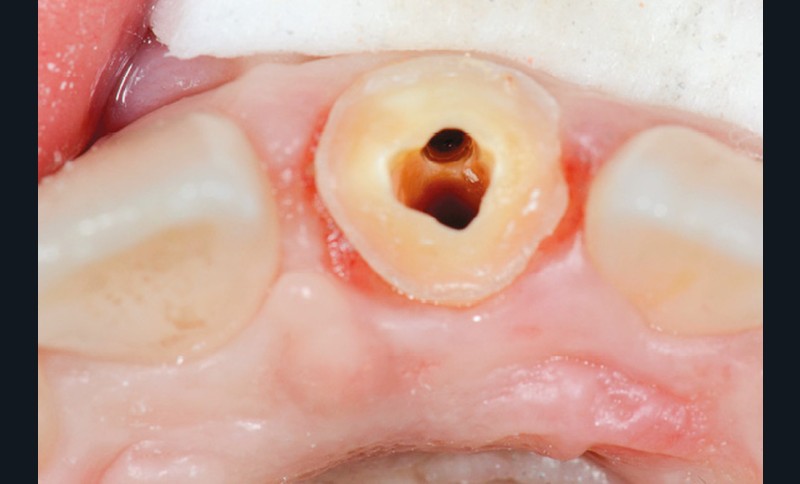

Une patiente de 18 ans, sans antécédents médicaux, se présente en consultation pour des douleurs à la pression au niveau de la 21. Cette dent a subi quelques mois auparavant un choc violent, qui a nécessité un traitement endodontique en urgence et la réalisation d’une couronne transitoire. L’examen clinique révèle une couronne transitoire à tenon (fig. 1 et 2).

La dépose de la couronne transitoire et du tenon métallique scellé confirme la présence d’un faux canal. Dès ce stade, le choix de la RCR amène une réflexion thérapeutique et s’intéresse à différents paramètres.